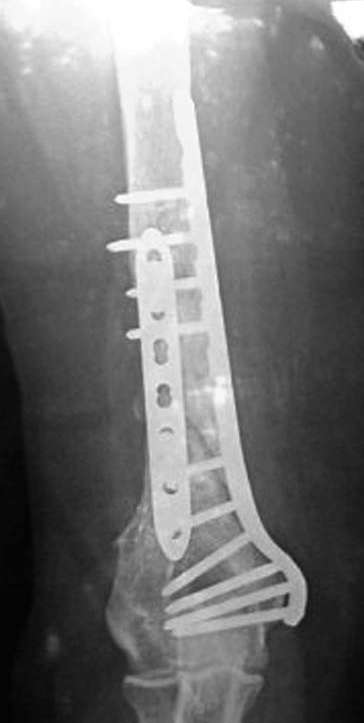

На примере два случая, извиняюсь за качество снимков, снимки и случаи из

Первая больная с "успехом" была прооперирована 6 раз различными методами

открытого и закрытого остеосинтеза, включая то, что в Кисловодске

заезжим австралийским "кудесником" на ложный сустав уложена скорлупа от

страусиновых яиц. Последняя операция одиноким локинг плейт в одной из

клиник.

Через год по поводу тех же проблем сделали ревизию, оригинальную

пластину оставили как есть, только укрепили добавлением еще одной

пластины и сделали костную пластику.

Через два месяца увидели признаки консолидации.

Имя     : 1 mukh ap nonunion.jpg

Тип     : image/jpeg

Размер  : 25118 байтов

Описание: отсутствует

Url     : http://weborto.net:8080/pipermail/ortho/attachments/20080223/b621f987/attachment-0006.jpg